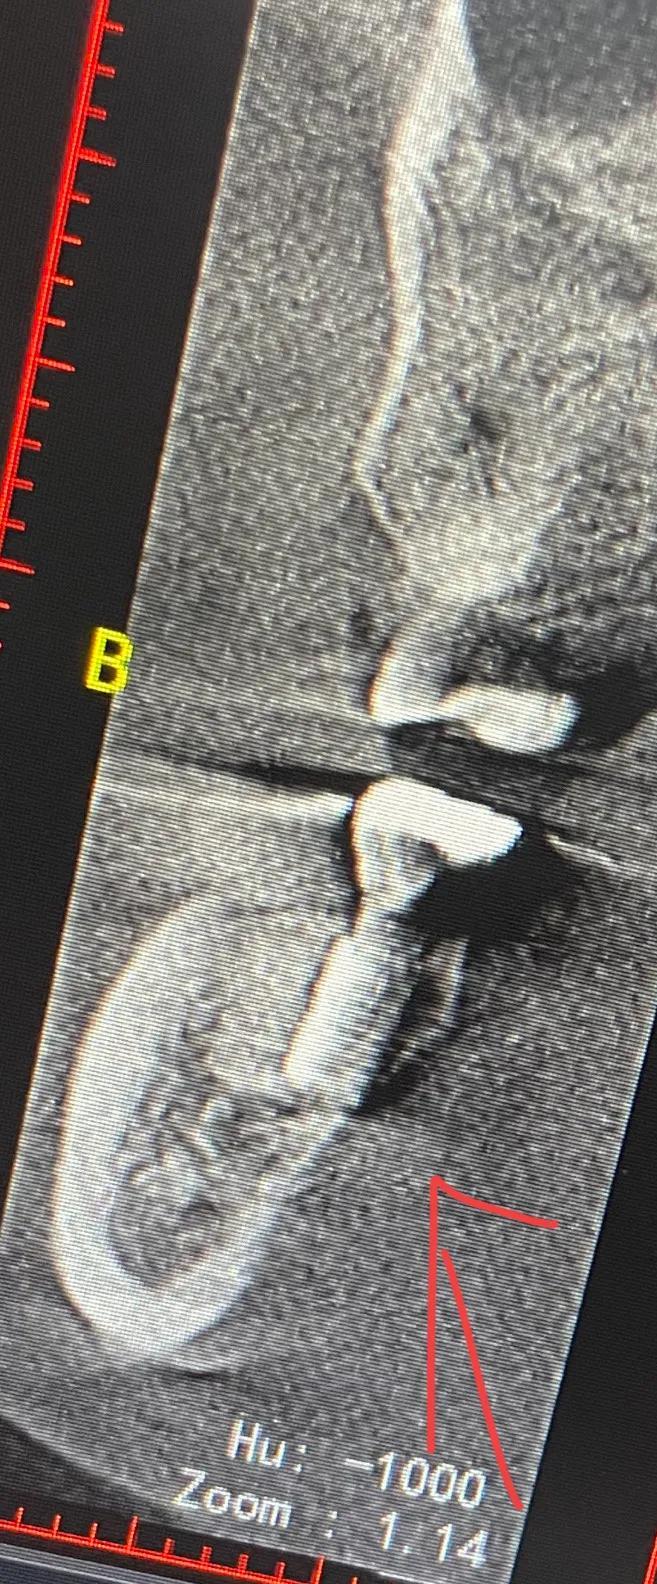

幾天后醫(yī)生?說把牙冠拿下來從新做 在那么劇烈的疼痛下 但凡醫(yī)生能早點(diǎn)?找一下原因 也不會(huì)遭這么大的罪 去其他醫(yī)院拍片子 說是?有骨頭高于種植體

戴上牙冠 多出來的骨頭在牙冠和種植體中間擠壓 所以會(huì)疼

沒辦法自己又出去拍片子 找原因 看了幾家醫(yī)院 才知道連種植體也種偏了 牙冠也沒有就位………